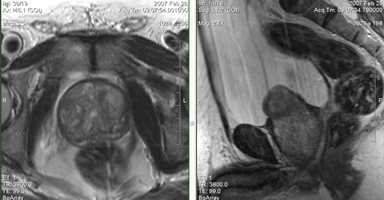

5. Агенезия семенного пузырька.

Рис. 35. Мужчина, 31 год с бесплодием. На Т2-аксиальном изображении определяется отсутствие левого семенного пузырька при наличии левого семявыносящего протока (стрелки).